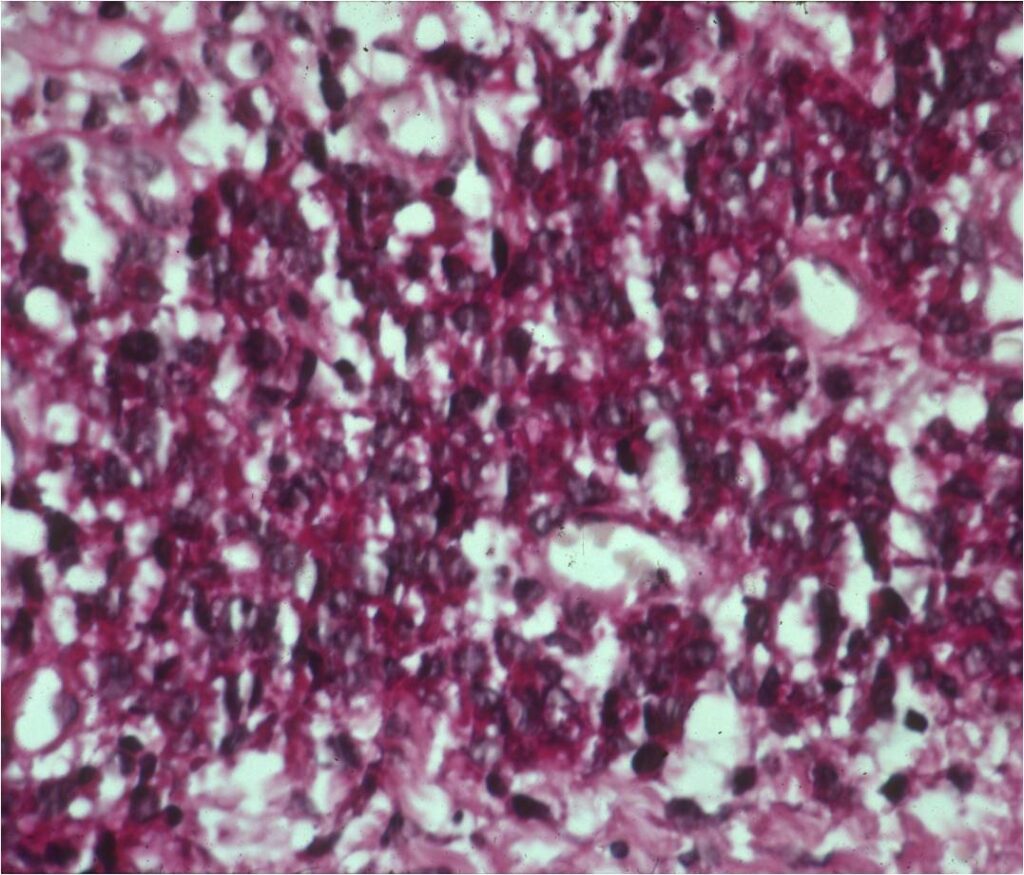

Microscopic Pathology

- Ewing sarcoma is composed of undifferentiated, small round, polygonal mesenchymal cells rich in glycogen

- Sheets of uniform cells with scanty pale cytoplasm and indistinct cell boarders

- No Matrix

- Nuclei are round/oval with finely dispersed chromatin

- Virtually no cytoplasm

- Areas of necrosis

- Variable number of mitoses

- Cells are similar in appearance

- Geographic necrosis with perivascular sparing

- Metaplastic bone or cartilage formation

- Chromosomal Translocation t(11;22)(q24;q12)

- PAS (glycogen positive); Reticulin stain poor

- Immunostains: Vimentin (+), CD99 (+); Leukocyte Antigen Negative

- Overexpress MIC2 detected by CD99

- Does not express neuroectodermal antigens

Small Round Blue Cells No Matrix Large Nuclei No Cytoplasm